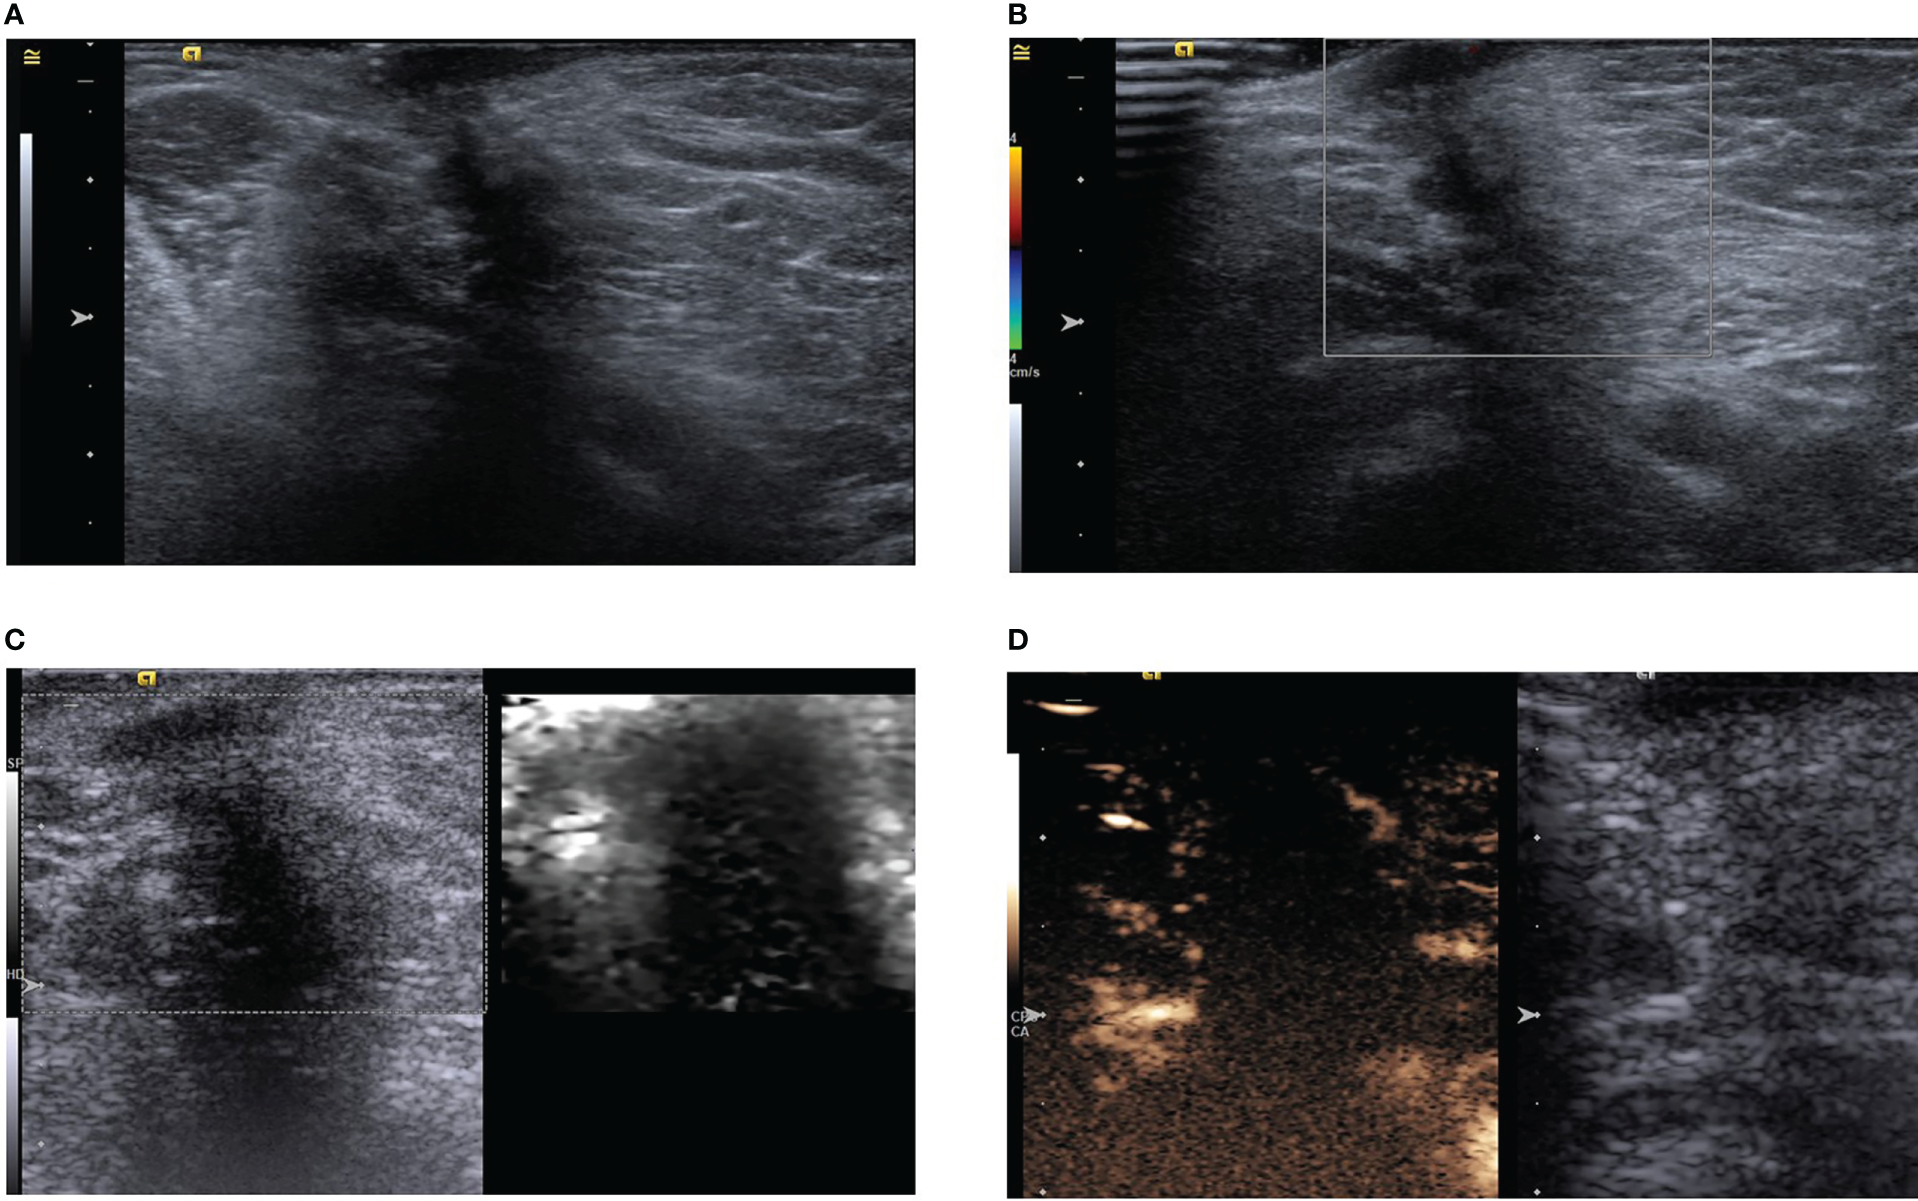

A 52-year-old woman had a palpable left axillary mass for a year before she visited our hospital. Although the patient denied any sensation of pain in the mass; abnormally red, swollen skin with discharge and progressive changes were observed. The patient had no relevant history of familial breast cancer or previous interventional procedures. A physical examination revealed a palpable, hard-textured mass of approximately 1.5×1.5 cm at the left axilla in proximity to the skin. The skin on the surface of the mass was ulcerated. No palpable right axillary or bilateral supraclavicular lymph nodes were found. The mass was not apparent on mammography. Subsequently, the patient underwent ultrasonography revealing a solid subcutaneous soft tissue mass of approximately 13×9×15 mm in the axilla, with unclear boundaries, irregular shape, and an aspect ratio greater than one (Figure 3A). Color Doppler ultrasonography demonstrated a lack of blood vessels in the mass (Figure 3B).

Figure 3

(A) Ultrasound showing a hypoechoic subcutaneous mass in the left axilla with an aspect ratio greater than one and acoustic shadowing. (B) Color Doppler shows no obvious blood supply in the mass. (C) Acoustic radiation force impulse model. (D) In the arterial phase, the tumor is slightly enhanced in the periphery, but not in the interior.

Multimodal ultrasonography was performed with the same ultrasound machine and settings used in case one. The ultrasound elastography revealed a hard-textured mass (Figure 3C) and contrast-enhanced ultrasonography indicated low enhancement in the peripheral part of the mass but no enhancement in the interior during the two minutes of continuous observation (Figure 3D). CEUS further revealed the possibility of potential benign lesions.